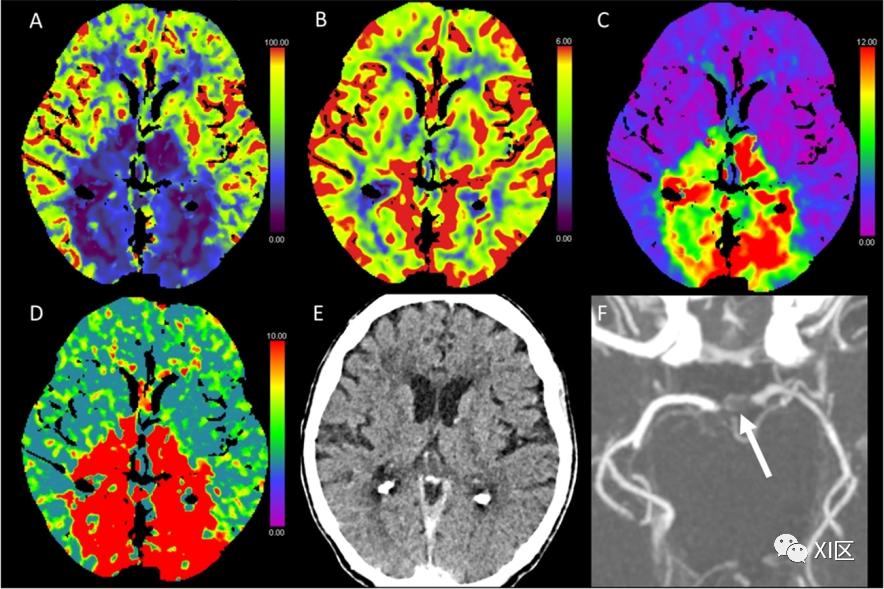

图1、图2、图3和图4给出了急性幕上卒中的例子。图5是一个恶性右侧MCA梗死的随访检查。

图2 脑部CTP生成的彩色编码图:(A)脑血流量(CBF)[mL/100 g/min],(B)脑血容量(CBV)[mL/100 g],(C)Tmax [s],以及(D)平均通过时间(MTT)[s]。(E)NECT和(F)动脉CT血管成像(CTA)。该患者在经导管主动脉瓣植入术(TAVI)后出现了左侧的暗区。在NECT图像上,只有大脑皮层有轻微的低密度改变,右枕部皮层有轻微的脑肿胀。CTP显示该区域的CBF和CBV降低,Tmax和MTT延长。CTA图像上没有发现明显的血管闭塞。